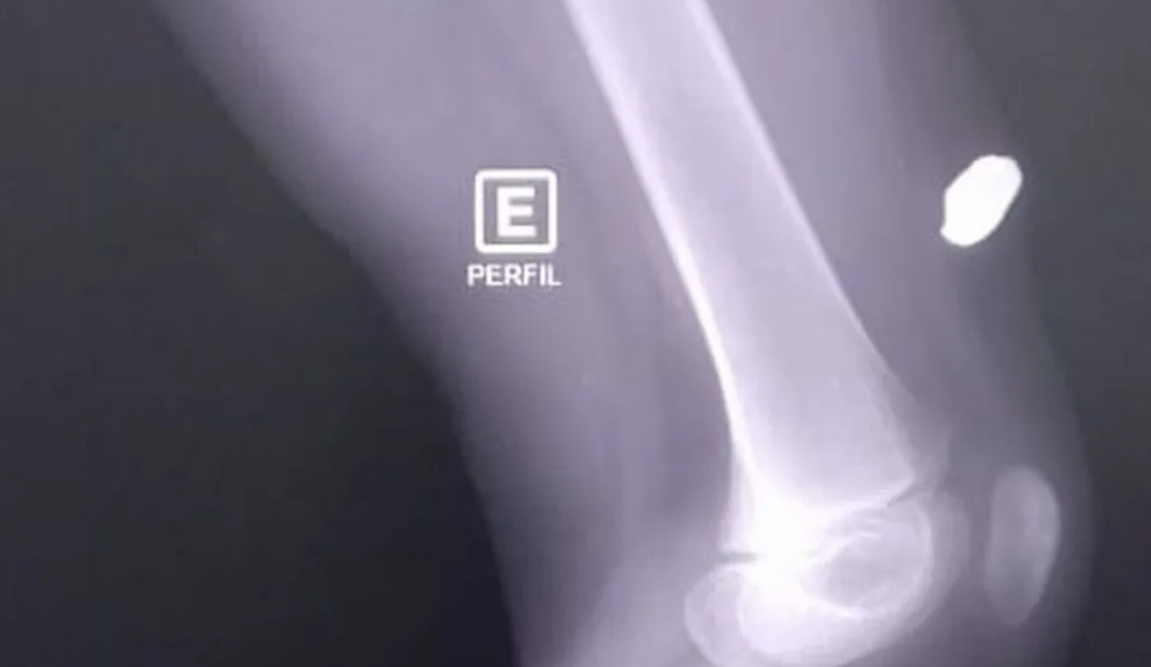

O caso ocorrei por volta das 7h. A bala ficou alojada na perna da criança, que vai passar por cirurgia. “Eu acordei com aquele estalo, eu pensei que tinha quebrado alguma coisa. Ele começou a gritar, desesperado, dizendo ‘Estourou alguma coisa aqui na cama, porque está sangrando a pena dele’. Quando eu fui olhar, a bala estava lá. Fomos olhar quem estava na rua, vimos a viatura. Na hora, eu saí gritando aqui, acho que eles não ouviram. Acho que eles não ouviram e saíram na viatura”, contou a mãe, que não quer ser identificada.